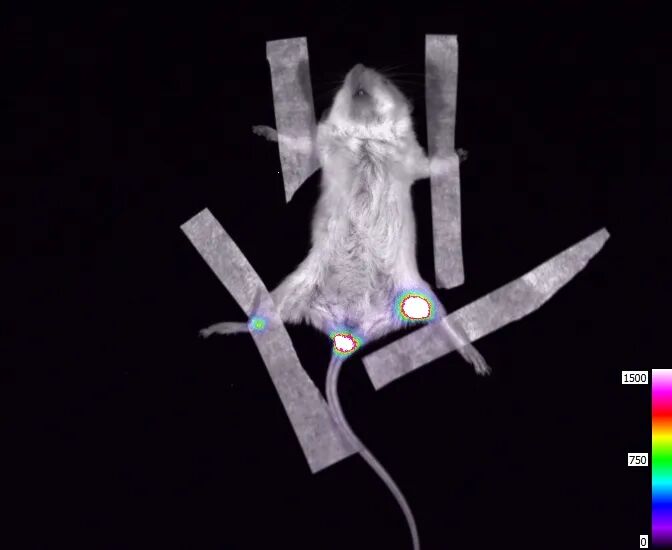

细胞治疗领域:如皮肤原代细胞的移植

①体外实验-3×105个转染荧光素酶报告基因的小鼠表皮原代细胞,外加底物荧光素,重复三次,可见重复性较好。

(使用CLINX IVScope 8500拍摄)

②体内实验-C57BL/6小鼠皮下注射3×105个转染荧光素酶报告基因的小鼠表皮原代细胞,随后腹腔注射底物荧光素,注射区域可见明显信号。